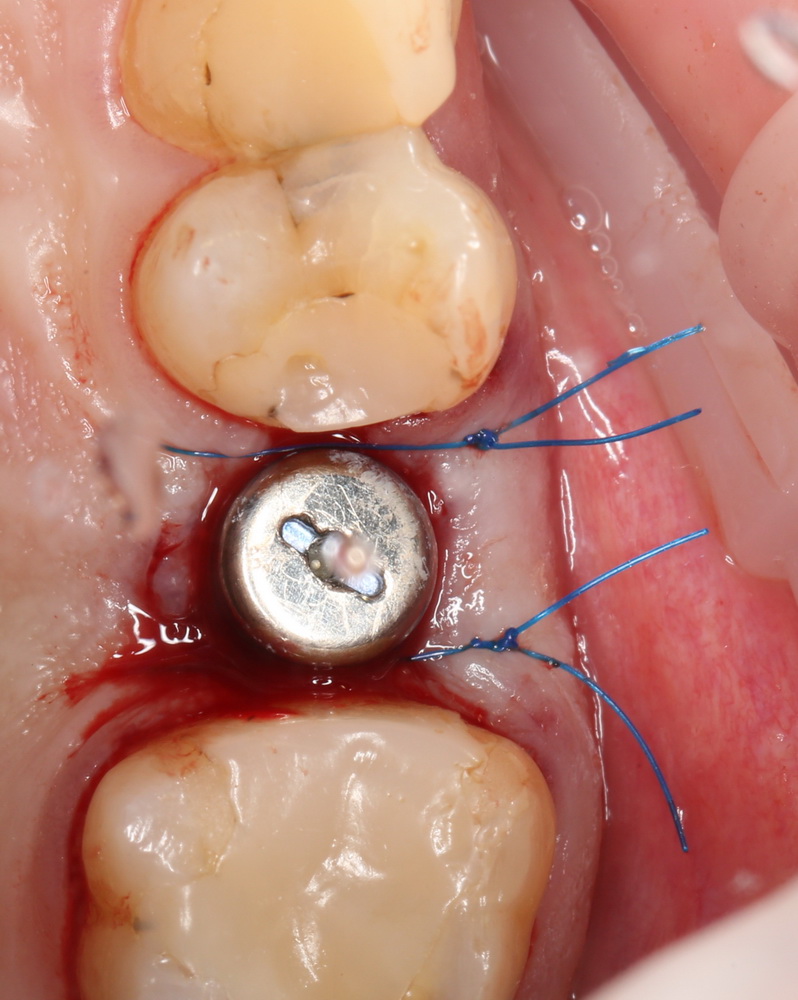

Но в данном случае стабильность хорошая, на имплантат фиксируем формирователь десны, накладываем швы:

Еще один важный момент. Не нужно пытаться стянуть рану и добиваться плотного прилегания десны к формирователю. Любое натяжение слизистой оболочки ведет к ее изменению (прикрепленная десна становится подвижной), а процессы атрофии костной ткани ускоряются. Чем меньше тянем и перемещаем — тем лучше. Поэтому вполне разумно оставить вокруг формирователя открытую рану шириной 0.5-1.5 мм, она нормально заживет вторичным натяжением.